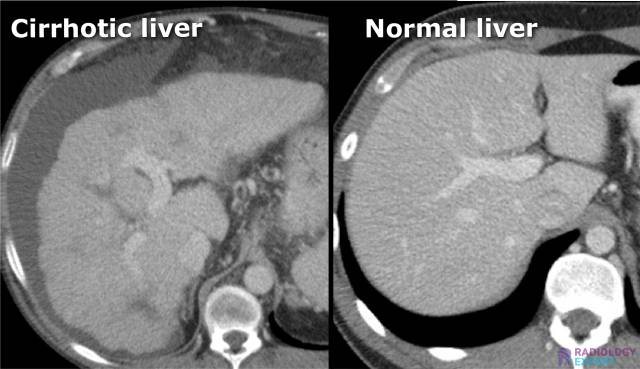

• Cirrhotic liver

Abdominal CT examination: liver cirrhosis Abdominal CT examination: liver cirrhosis